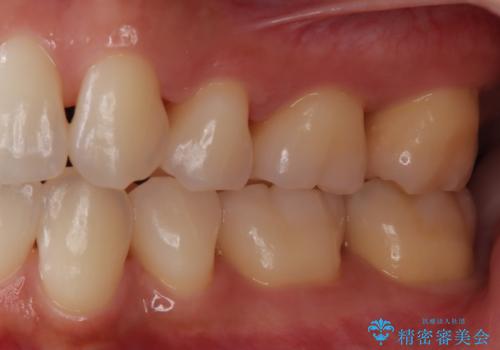

- 定期的にクリーニング(保険適応)に通って頂いている患者さんです。歯周ポケットが4ミリあったため歯茎を開いて歯石を除去するためにオープンフラップ術を行うことにしました。

歯周ポケットがそれほど深くない患者さんでしたが、いざ歯茎を開いてみるとそこにはたくさんの歯石がありました。もし歯周ポケットが4ミリだからと言って放置していれば数年後には、沢山の骨が無くなっていたことが予期出来ます。現段階で歯茎の下にある歯石を除去することにより骨が無くなることを予防する事が出来ました。